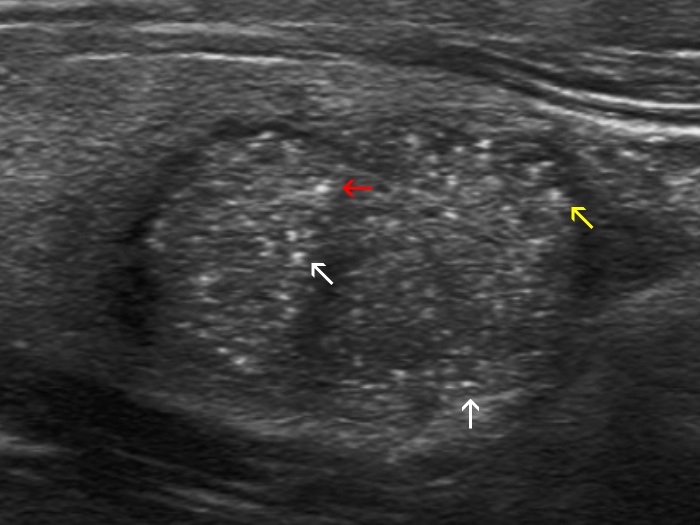

Intranodular hyperechogenic figures - case 2174 (ultrasonographic picture 2b)

Right lobe, longitudinal view, enlargement. Some of the echogenic granules are located dorsal to more hypoechoic areas (white arrows), which raises the possibility of back wall cystic enhancement as a cause of these figures. At least one of the granules has a dorsal tail (yellow arrow). On the other hand, the punctate echogenic focus (marked with a red arrow) fulfills the criteria of microcalcification.